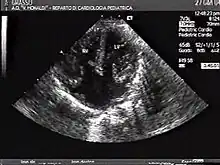

The proper development of the atrioventricular canal into its prospective components (The heart septum and associated valves) to create a clear division between the four compartments of the heart and ensure proper blood movement through the heart, are essential for proper heart function. When this process does not happen correctly, a child will develop atrioventricular canal defect which occurs in 2 out of every 10,000 births.[1] It also has a correlation with Down syndrome because 20% of children with Down syndrome have atrioventricular canal disease as well. This is a very serious condition and surgery is necessary within the first six months of life for a child.[2] Half of the children who are untreated with this condition die during their first year due to heart failure or pneumonia.[3]

In a normal heart there are four chambers. These are the right and left atria, and right and left ventricles. The right atrium and right ventricle function to pump blood to the lungs while the left atrium and left ventricle pump blood to the rest of the body. There are heart valves in place that inhibit back-flow between these chambers.[4]

Atrioventricular canal defect may be divided into partial or complete forms. In the partial form, openings between the left and right atria and improper formation of the mitral valve exist. In the complete form, there is free movement in all chambers because there is a large hole where the atria and ventricles meet, and instead of there being two valves there is one common valve.[4]